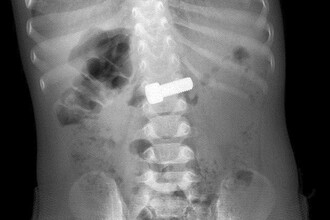

Годовалый ребенок попал в больницу, проглотив металлический болт